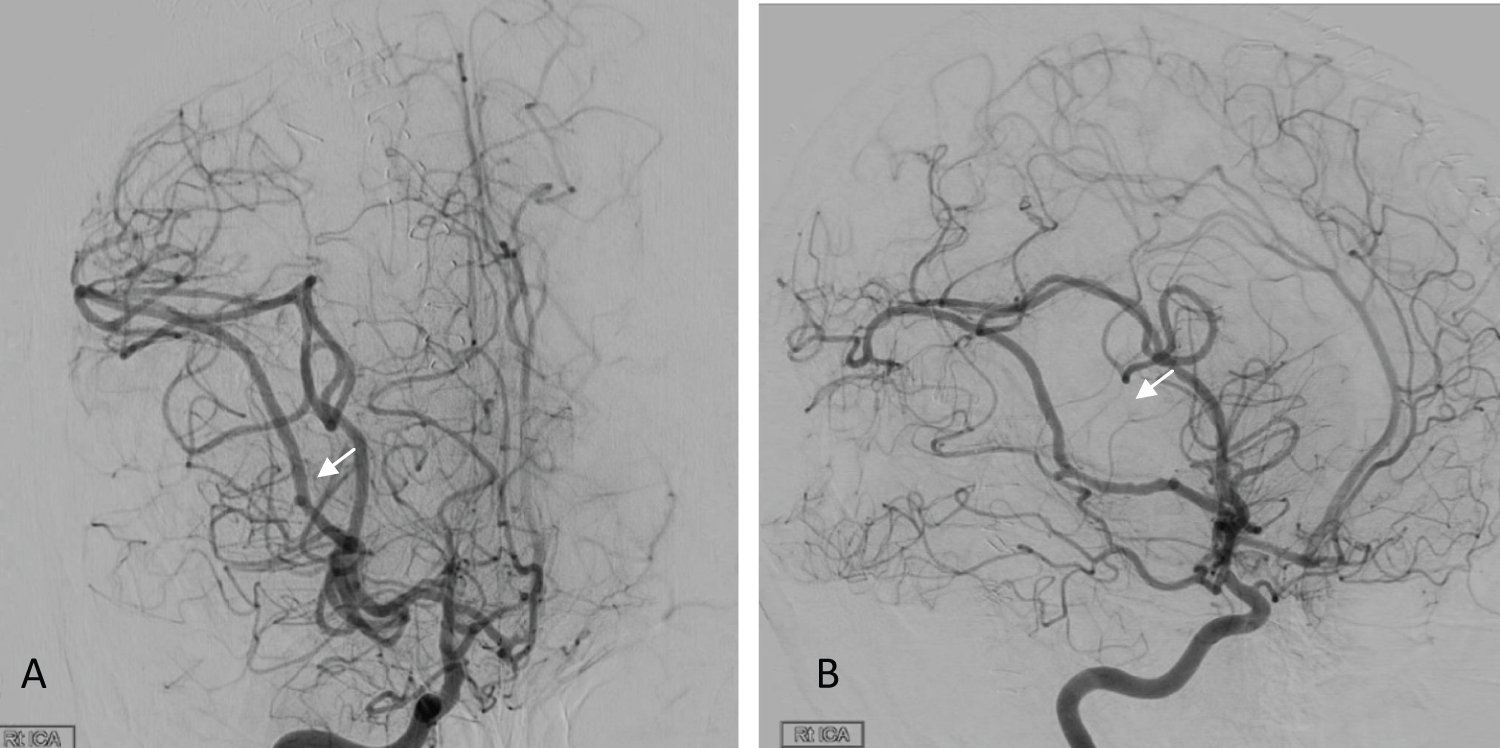

Postoperatively, the patient was kept in the neurocritical care unit (NCCU), where she was sedated and intubated as elected by the anesthesia team due to the long operating time. The next morning, she was still intubated, off sedation and maintaining a Glasgow Coma Scale of 11/15 with reactive pupils, and she could move all limbs freely. On postoperative day 2, she was shifted to the floor with a GCS of 15/15 and no motor or sensory deficits. MRI was obtained (Figure 3); there was debulking of the large lesion in the right frontotemporal area, and residual tumor tissue was seen along the margins of the cavity. There were no territorial ischemic changes. Prior to discharge, cerebral angiography was performed to evaluate the patency of the vessels and to exclude any major radiographic stenosis (Figure 4).

Figure 4: Postop angiography; right ICA injection AP and lateral view (A,B) showed a filling delay of the insular branch medial to the tumor (Arrows) with distal filling likely from collaterals; the rest of the middle cerebral artery branches are patent, with no aneurysmal formation or vasospasm. View Figure 4